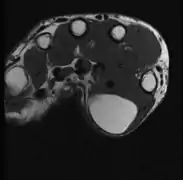

MRI showing lipoma of the arm